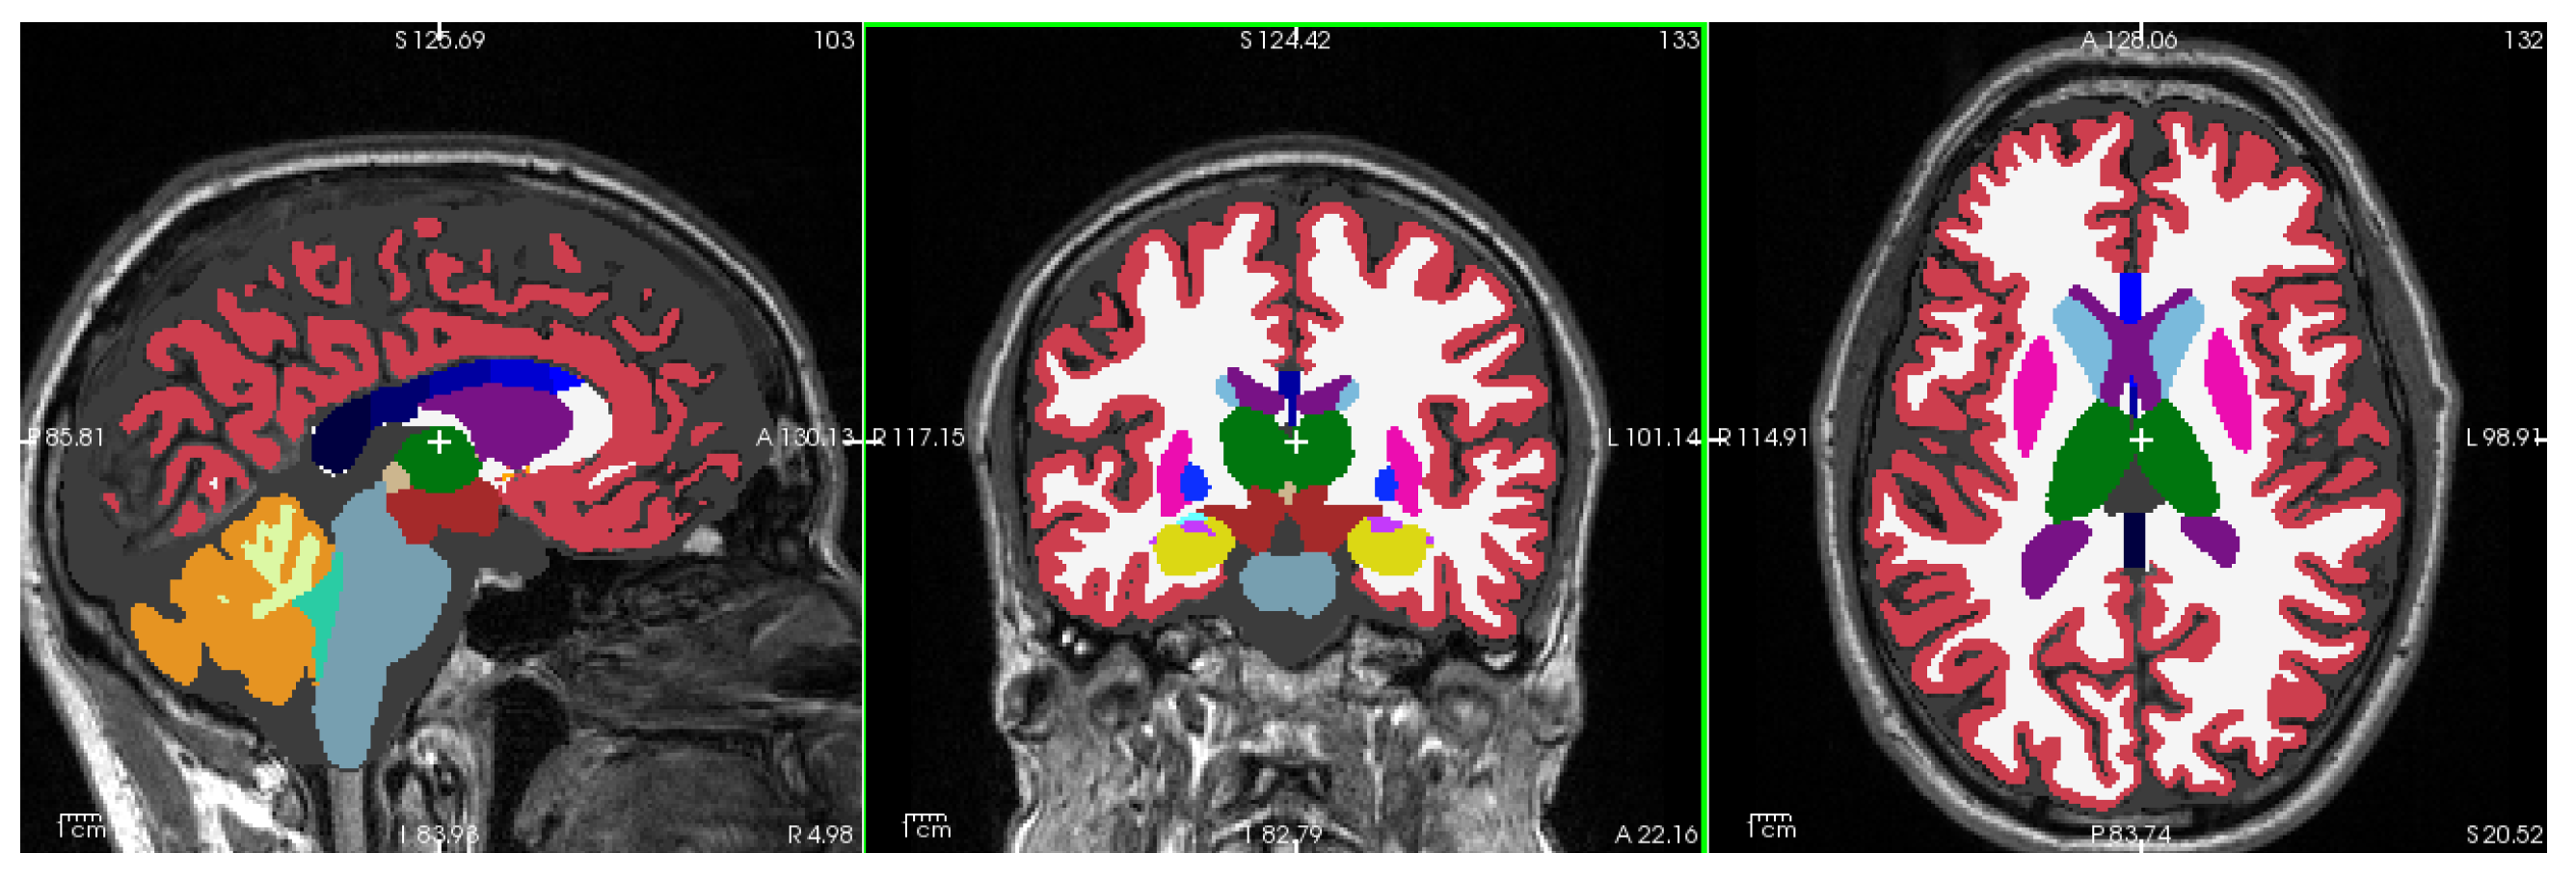

Figure 1 shows a representative T1-weighted image from our dataset, demonstrating the high tissue contrast necessary for accurate morphometric analysis. The corresponding FreeSurfer-generated segmentation mask, which forms the basis for our morphometric measurements, is illustrated in Figure 2. These images exemplify the quality standards maintained throughout our dataset.

2.4. Brain Morphometry Analysis Using FreeSurfer